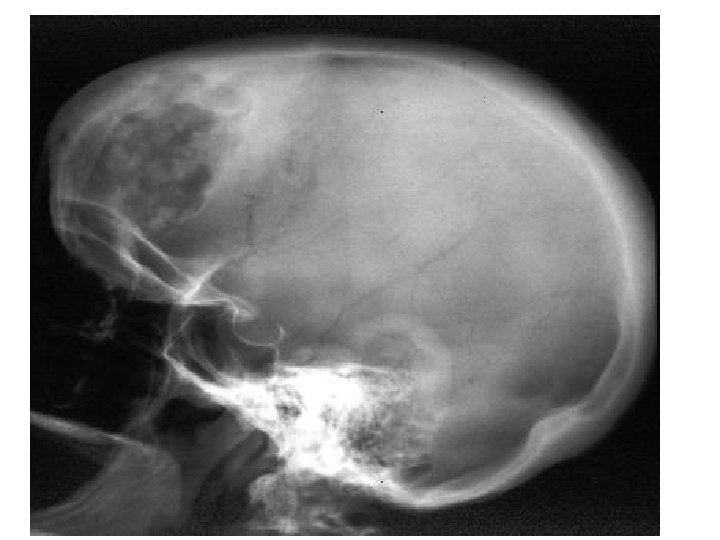

Rickets • Rickets is the softening and weakening of bones in children, usually because of an extreme and prolonged vitamin D deficiency. • Some skeletal deformities caused by rickets may need corrective surgery.